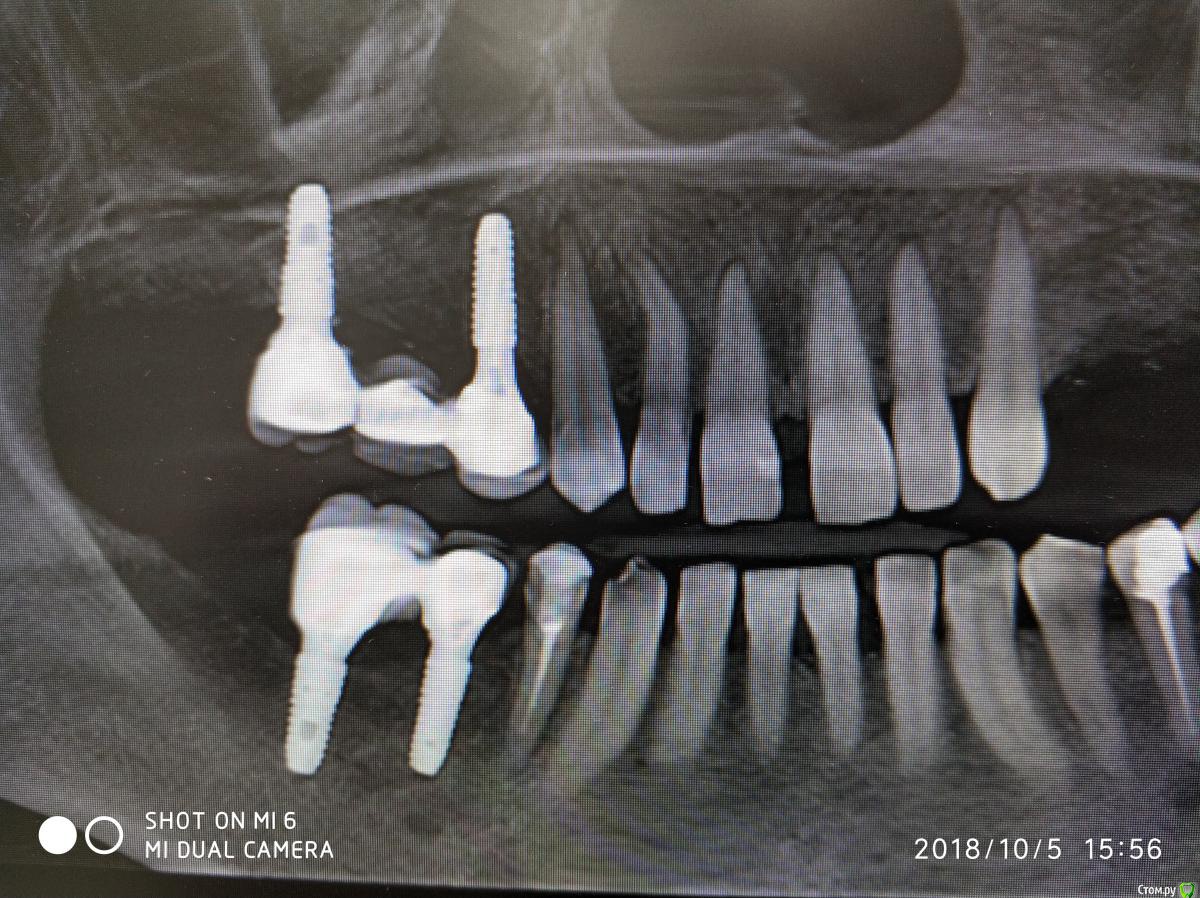

Nazim_NV86 Опубликовано 7 августа, 2018 Автор Поделиться Опубликовано 7 августа, 2018 14-16 с синусом стоят год, стоит металлокерамика. 45,46 пока с фдм. Осстем. Ссылка на комментарий

Nazim_NV86 Опубликовано 11 октября, 2018 Автор Поделиться Опубликовано 11 октября, 2018 Появилась свежая КЛКТ Ссылка на комментарий

Nazim_NV86 Опубликовано 11 октября, 2018 Автор Поделиться Опубликовано 11 октября, 2018 (изменено) Женщина. Примерно 50-53. Скрины синуса сделал, но замотался и забыл выложить. Синусы вч оба чистые. Слева правда есть маленькое мукоцеле. Сегодня предложил ей снять коронки и походить с формирователями. По семейным причинам уехала к дочери помогать. Отложили на месяц. Так у нас есть месяц на расследование ) Изменено 11 октября, 2018 пользователем Nazim_NV86 Ссылка на комментарий

Nazim_NV86 Опубликовано 2 февраля, 2019 Автор Поделиться Опубликовано 2 февраля, 2019 (изменено) В продолжении беседы:02.08.16г. была микрогайморотомия справа ( ДЗ выписке: киста г.п.).10.08.17г. поставлены 14,16 с открытым синус-лифтингом(апатос микс+эволюшн). Синус был чистый как до, так и после операции. Соустье работало.18.01.18г. поставлены 45,46. После операций никаких особенностей. 19.04.18г. 4 фдм. И примерно в это время (со слов) появились проблемы с запахами. Коронки сданы 29.05.18г.При допросе (настойчивом) оказалось что пациентка часто болеет ОРЗ и постоянно лечится. Аллергоанамнез оказался впечатляющий. В анкете об этом нет информации. Перечень всего на что у неё была аллергия большой. Попросил перечислить мне на бумаге.На контр осмотр не пришла, поскольку снова заболела. Иммуноглобулины: А - 0,39 (0,65-4,21); М - 0,72 (0,33-2,93); G - 18,64 (5,52-16,31). от 23.01.19г Попросил сдать сам.Заключение МРТ от 21.08.18г. МР-картина очагов глиоза в белом веществе головного мозга сосудистого характера, умеренной наружной заместительной гидроцефалии. Данных за объёмные патологические образования и ишемические изменения не получено. Жду результатов других анализов (направлял терапевт). Изменено 2 февраля, 2019 пользователем Nazim_NV86 1 Ссылка на комментарий